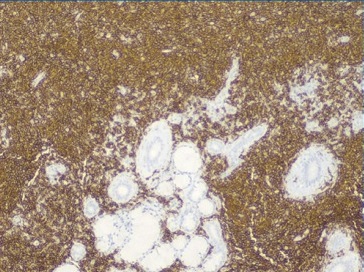

As hipóteses colocadas para diagnóstico diferencial desta lesão apresentadas foram tumores de células salivares (adenoma pleomórfico, carcinoma muco‑epidermoide e adenocarcinoma polimórfico de baixo grau), abcesso de origem dentária/endôntica ou de origem periodontal, e neoplasia linfoproliferativa. Deste modo, procedeu‑se à biópsia incisional que revelou, a nível submucoso, a existência de glândulas mucosas rodeadas por denso infiltrado de células linfoides com vago padrão nodular, assim como espessamento hialino acentuado periductal (Figura 4). Os linfócitos apresentavam tamanho pequeno a intermédio com núcleos hipercromáticos e irregulares, sem lesões linfoepiteliais. A análise imunohistoquímica, revelou expressão de CD20 generalizada com CD10 positivo em áreas nodulares, assim como BCL‑2 e BCL‑6 (Figuras 5, 6 e 7). Estas alterações eram compatíveis com linfoma B folicular, com envolvimento de glândulas salivares minor.

Figura 4 Anatomia patológica da biópsia incisional, revelando existência de glândulas mucosas rodeadas por denso infiltrado de células linfoides com vago padrão nodular